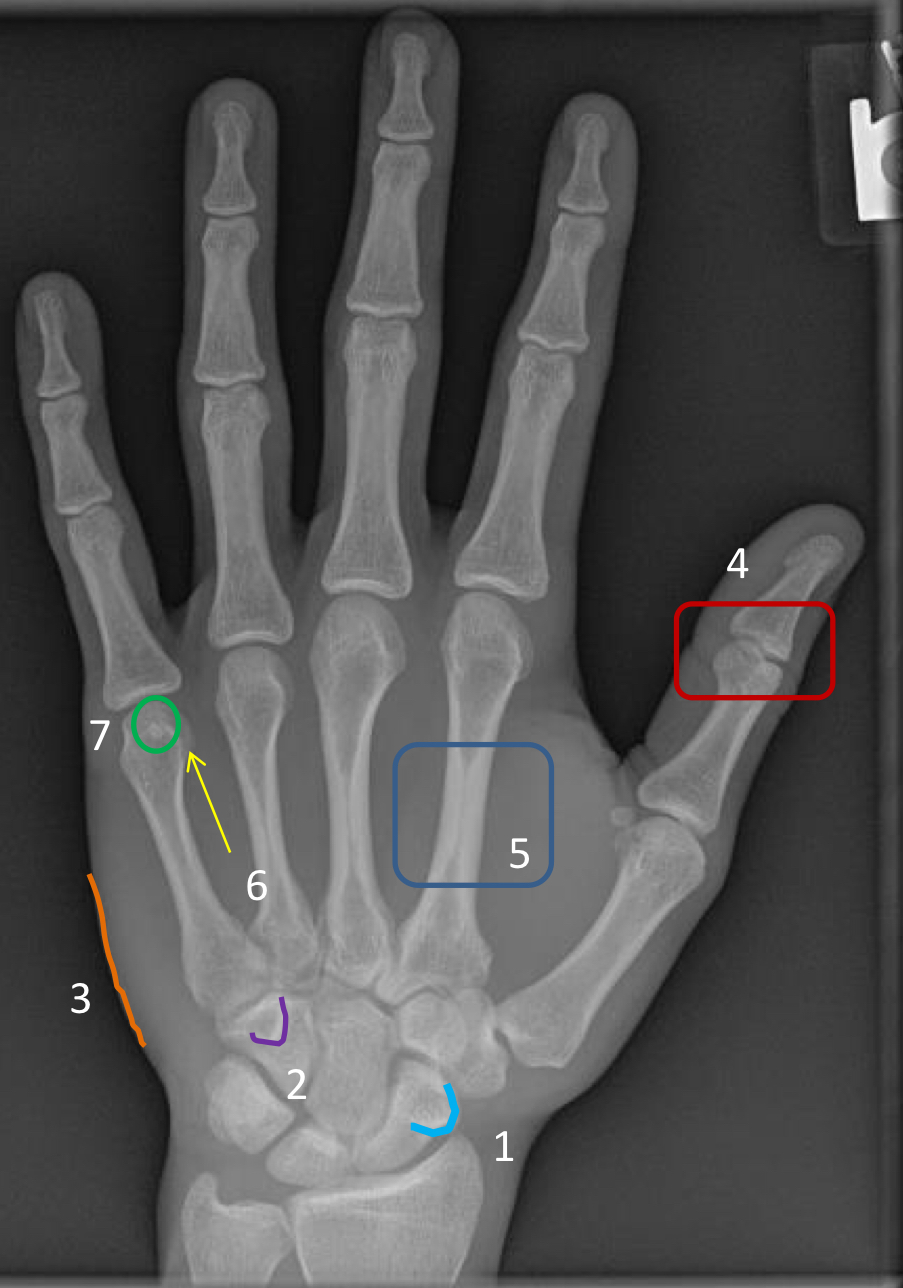

1?

scaphoid tubercle

2?

hook of hamate

3?

hypothenar eminence

4?

1st interphalangeal joint (poorly visualized)

5?

2nd metacarpal diaphysis

6?

“condylar” appearance at the head of metacarpal